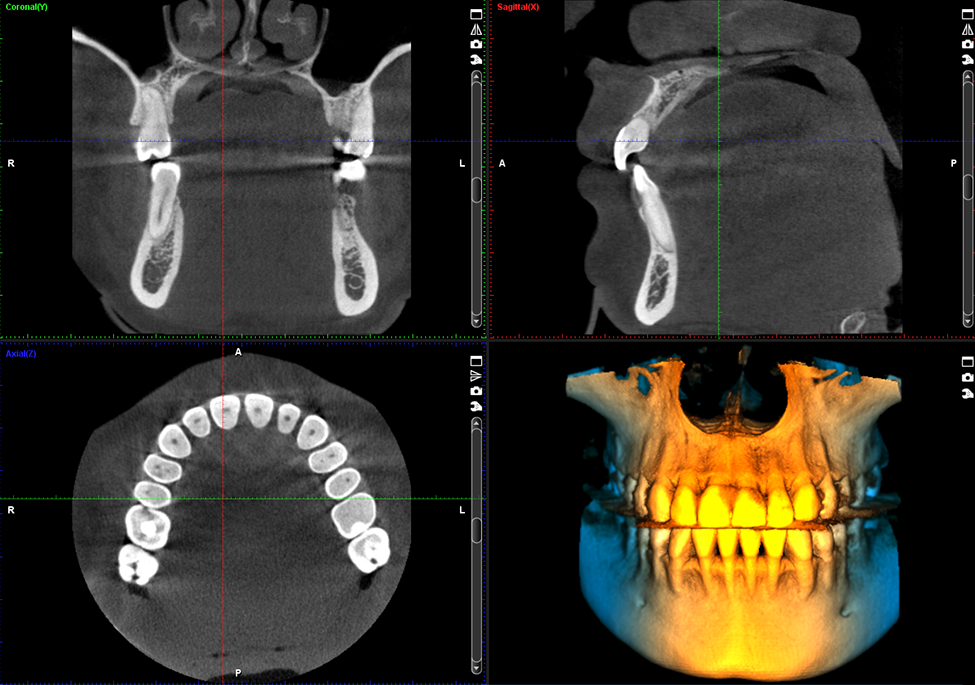

Planmeca ProMax® 3D Classic

Nuestra unidad Planmeca ProMax® 3D Classic cubre toda la dentadura, lo que la convierte en una excelente opción para las necesidades de imágenes 3D del arco dental completo

Nuestros equipos: Planmeca ProMax® 3D Classic

Calidad de imágen - Imágenes Tomográficas